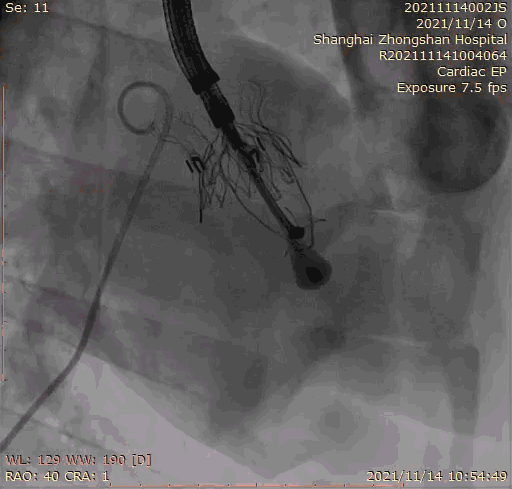

本次臨床前研究經右側頸靜脈置入LuX-Valve Plus輸送系統(tǒng)可調彎鞘管,在DSA及超聲引導下將人工三尖瓣瓣膜植入到原有三尖瓣位置,利用獨特的錨定技術將人工瓣膜支架可靠固定在預定的位置。

上海中山醫(yī)院葛均波院士、錢菊英院長、周達新教授、潘文志教授、潘翠珍教授、李偉教授共同完成此次臨床前研究。術后葛均波院士對Lux-Valve Plus的器械操作性能給予了高度評價,DSA和超聲影像也顯示出在本次研究中Lux-Valve Plus的安全性和有效性俱佳。